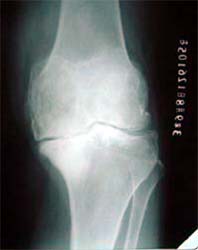

图:骨关节病晚期软骨破坏。

图:膝关节软骨碎裂、磨损,双膝内翻,X线片显示关节间隙消失

病例一、患者男性,76岁,双膝疼痛10年,屈伸受限,下蹲困难。线片显示双膝骨关节炎改变,关节间隙已经消失。严重膝内翻畸形。